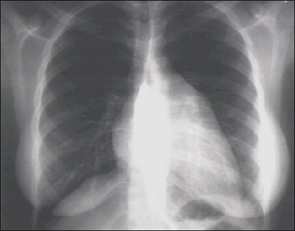

PA and Lateral

These are the PA and Lateral views of our patient's X rays for your intepretation

Choose the best interpretation of the chest X rays:

Left atrial enlargement & right ventricular enlargement

Marked left atrial enlargement

Right ventricular enlargement & markedly dilated pulmonary artery